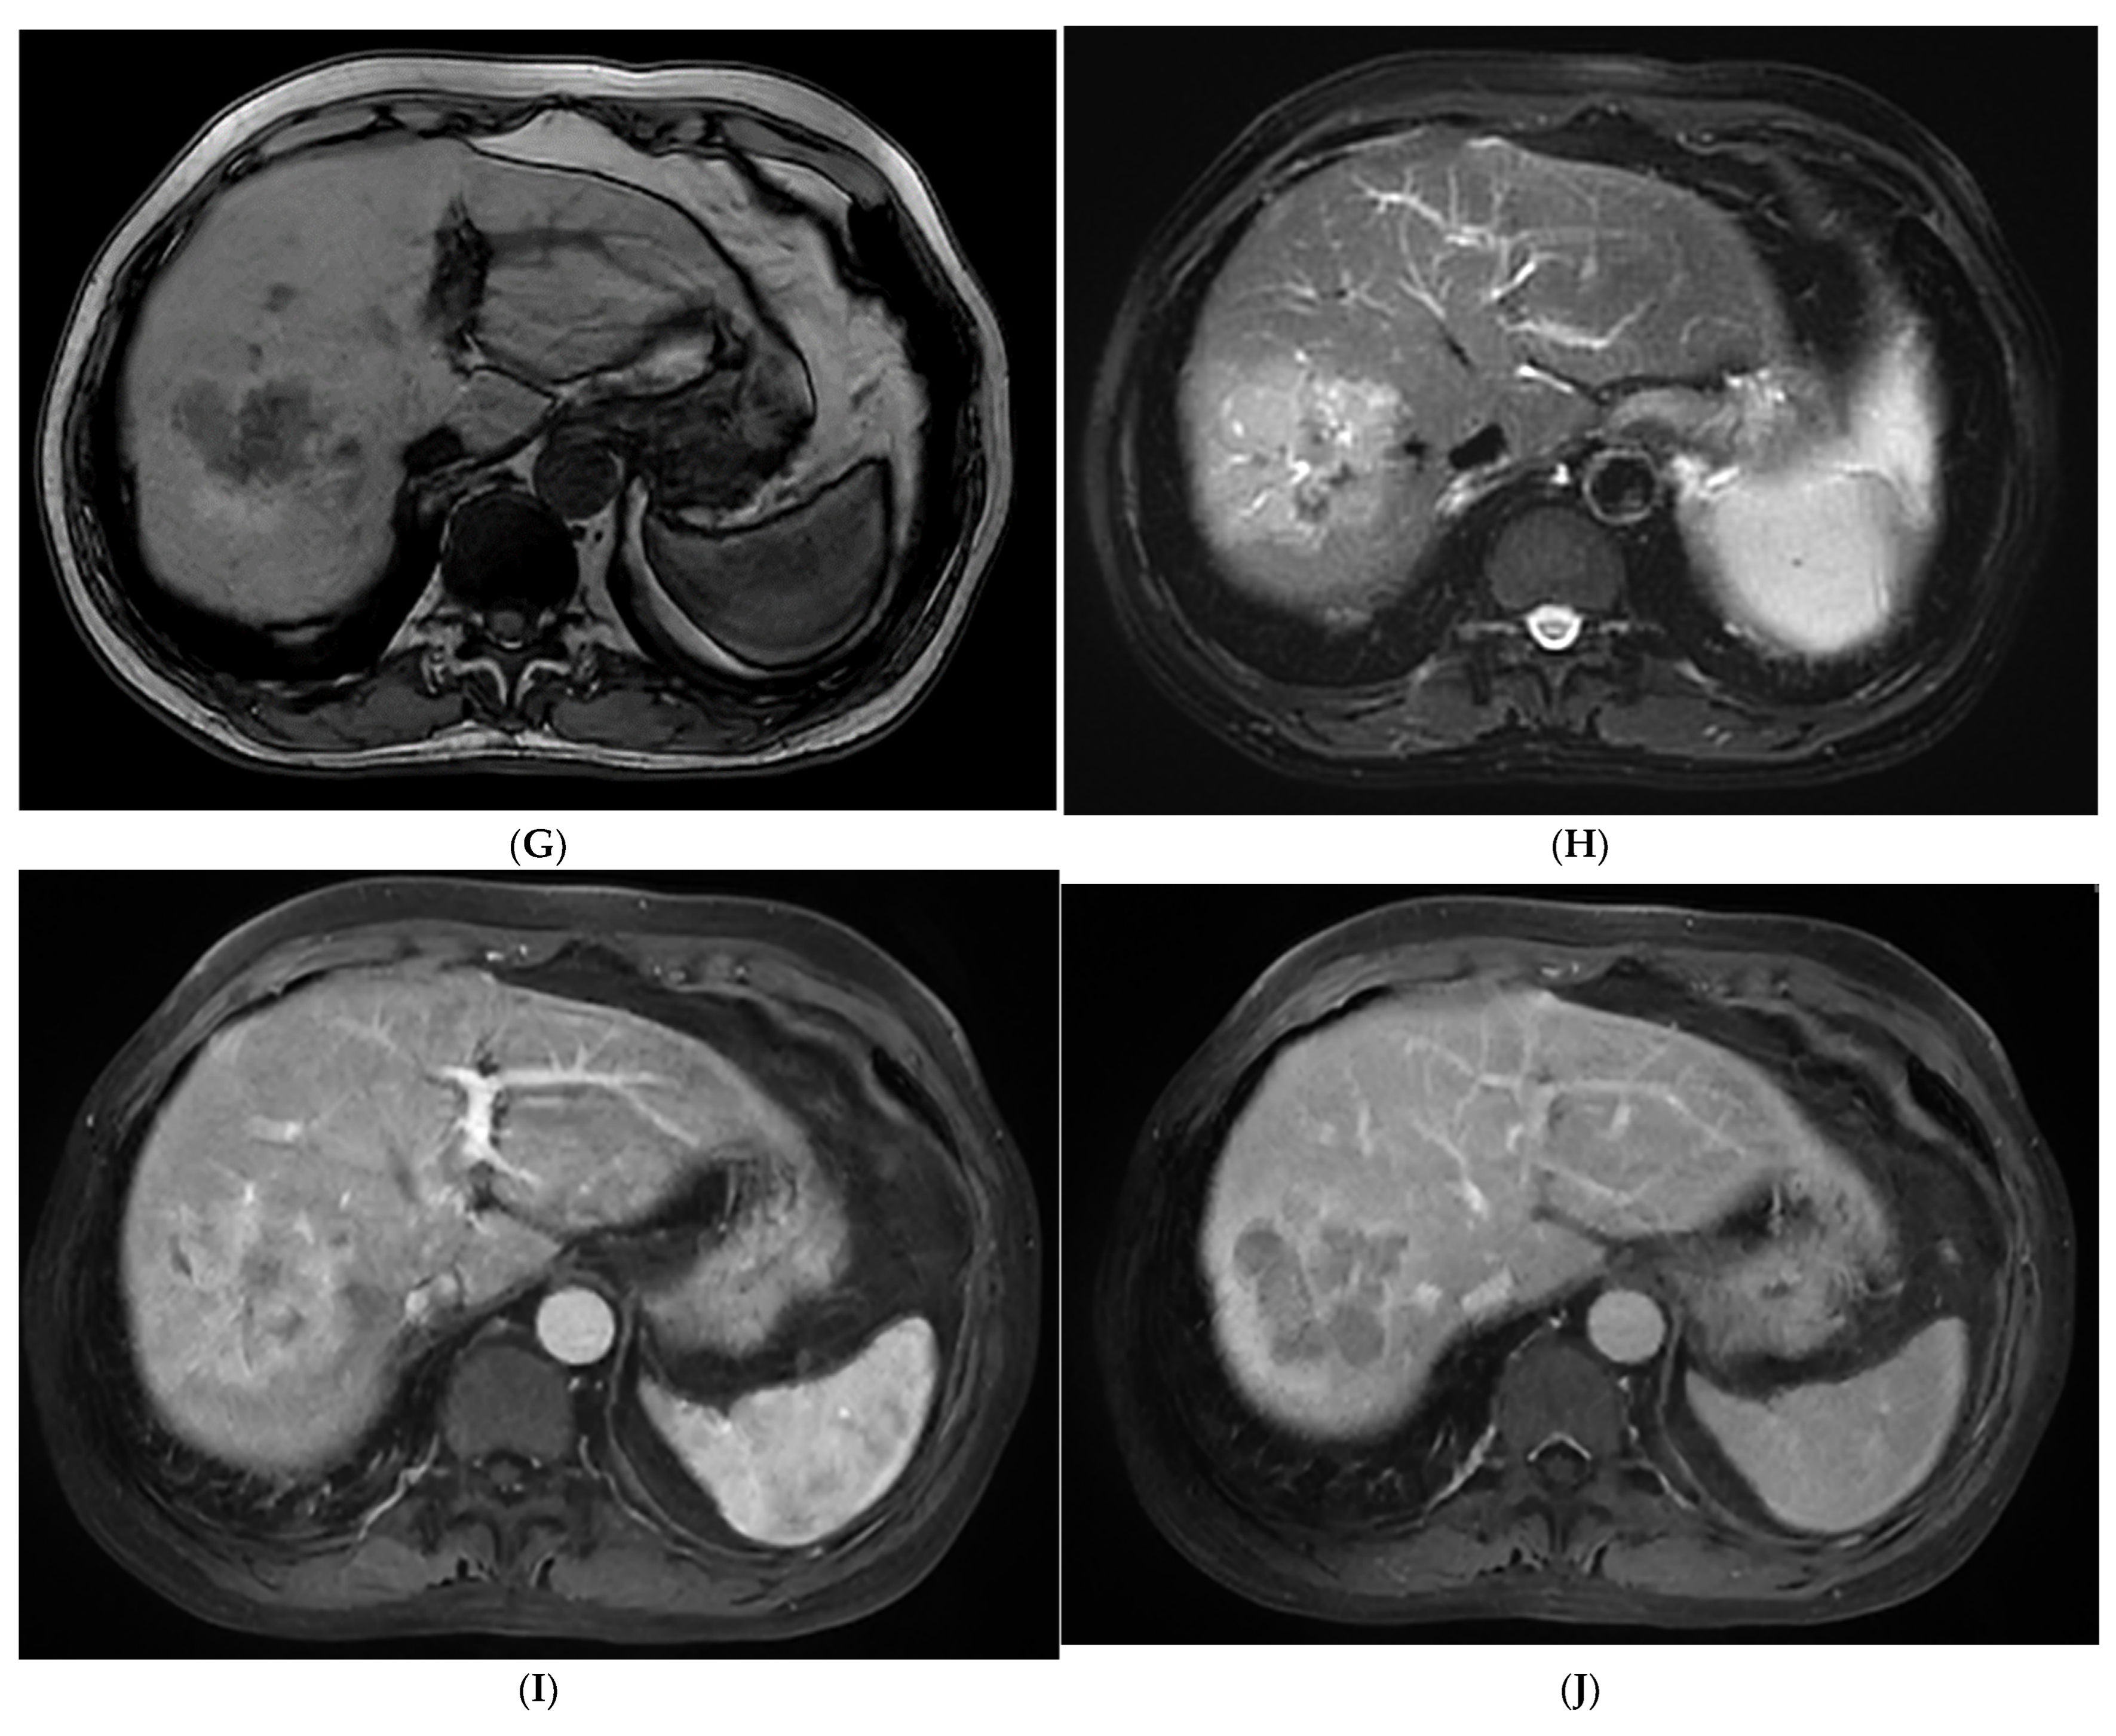

Figure 2.

The contrast-enhanced images of non-steatohepatitic hepatocellular carcinoma (non-SH-HCC). A hypo-echoic lesion in the right lobe of the liver was seen as seen via BMUS (A). In the early arterial phase of CEUS, the hepatic nodule was homogeneously hyperenhanced (B). During, it presented continuous iso-enhancement during the portal venous and late phase (C,D). On T1WI, the hepatic nodule was homogeneous hypointense (E). On T2WI, it was hypointense (F). As seen via con-trast-enhanced scan, the lesion showed hyperintensity in the arterial phase (G). It exhibited slight hyperintensity in the portal venous phase (H). During the late phase, the hepatic lesion started to show iso-intensity (I).